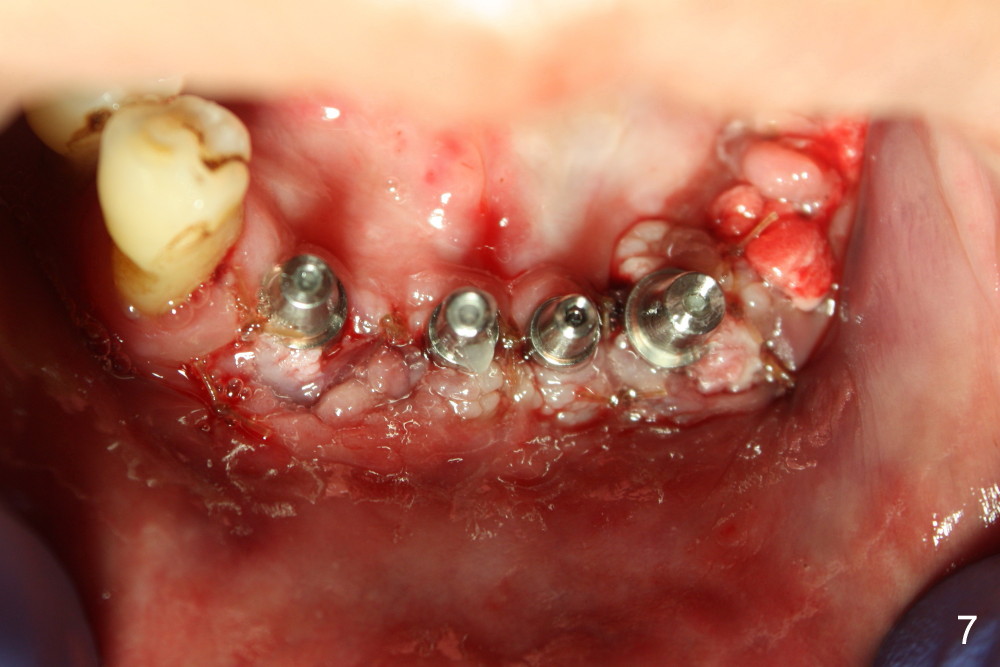

Osteotomy is initiated through the gingiva of the healing sockets at the sites of #22 and 27 (Fig.1) with difficulty (close surgery). The incisor crest incision is extended distal to the canine areas; an accessory oblique incision is supplemented to facilitate implantation (#22: 5x14 mm; #27: 4.5x17 mm) and expose the buccal defects (Fig.3,4, open surgery). The defects are grafted (Fig.5) and covered by collagen membrane (Fig.6). The incisions are closed and abutments are placed for immediate provisional (Fig.7).

Incision (open surgery) appears to help increase surgery safety and avoid complication (nerve injury) associated with immediate implant.